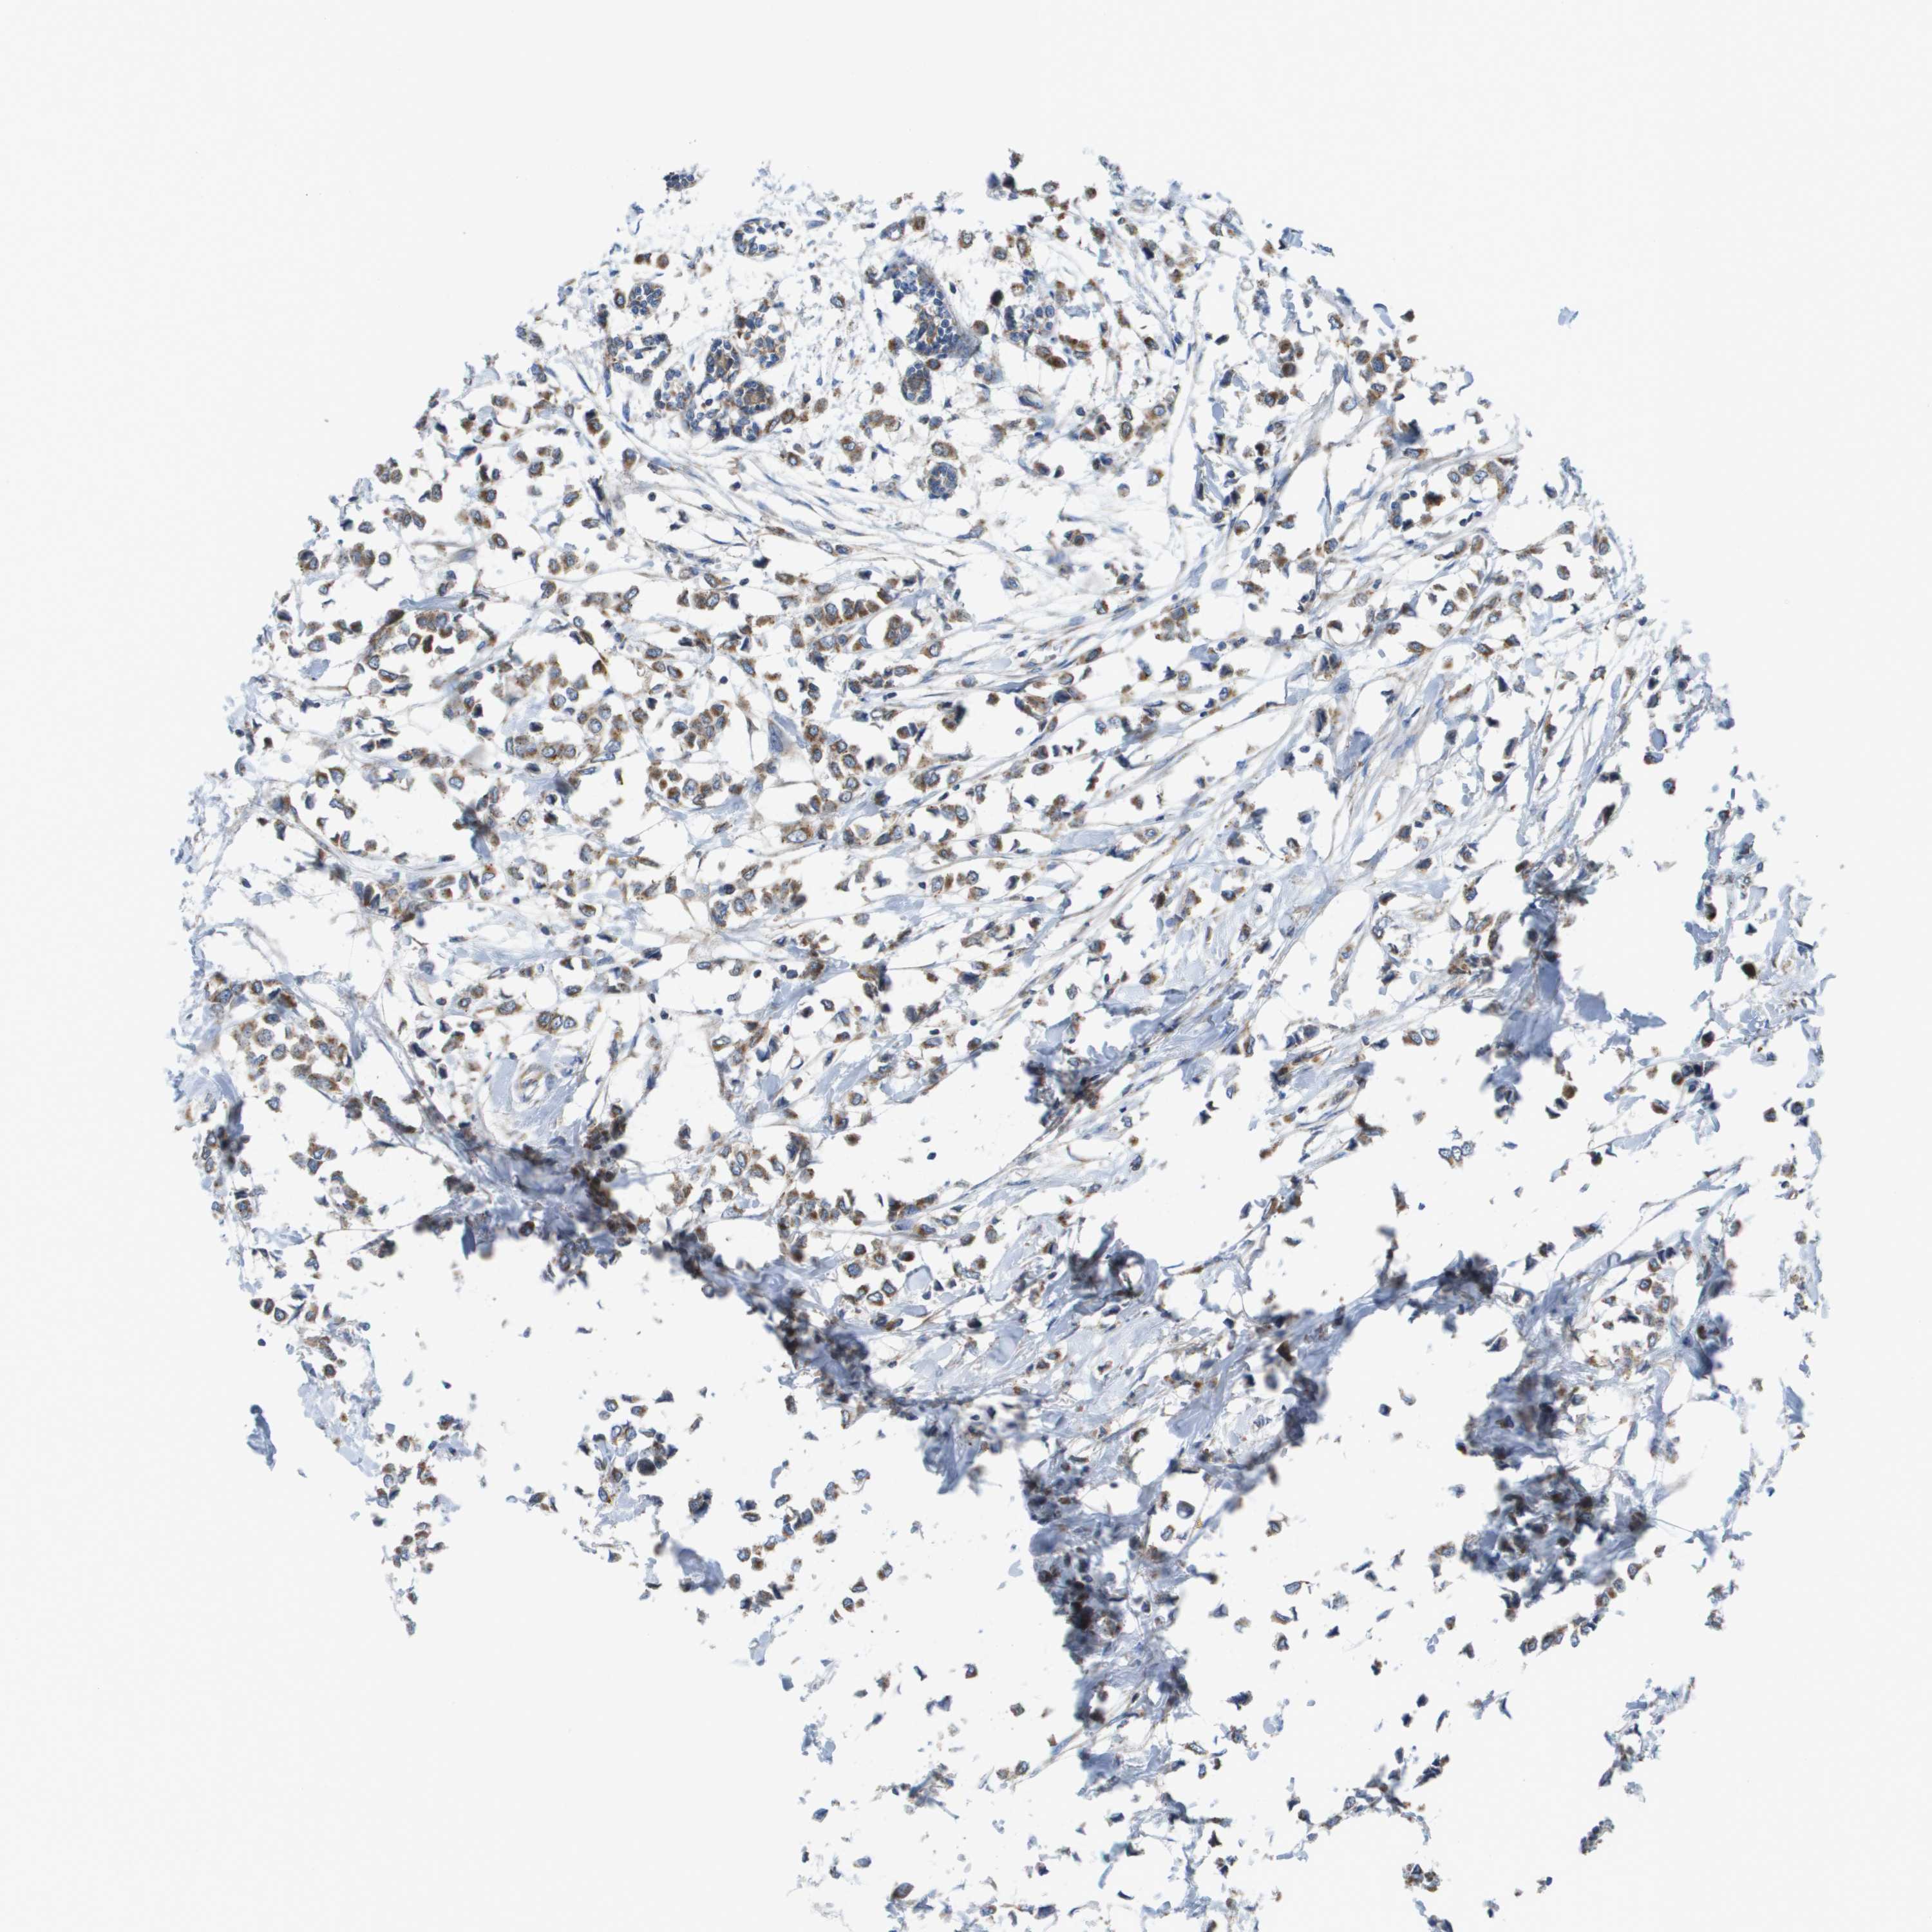

CANCER BREAST CANCER Show tissue menu

BRCA TCGA BRCA VALIDATION PROTEIN EXPRESSION

ANTIBODIES

AND

VALIDATION